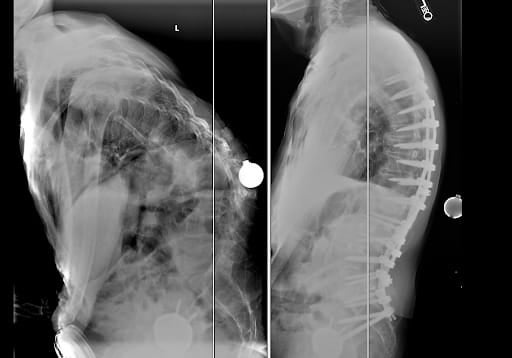

spine surgery before and after x-raysFor Dr. Villar, Michael’s case was a reminder of why he chose to specialize in spine conditions. He expressed how these advanced, complex cases inspire his work and passion to provide dedicated care to his patients.

spine surgery before and after x-raysTo correct Michael’s condition called Kyphoscoliosis, Dr. Villar performed a spinal alignment procedure to help him stand upright. After the surgery, Michael stayed in the hospital for about a week and then spent two more weeks at an inpatient rehab center. By the time he returned home, he was walking again with steady progress each week. “Seeing him return to daily activities has been incredibly meaningful, his whole demeanor has changed. He cannot stop smiling!” said Dr. Villar.